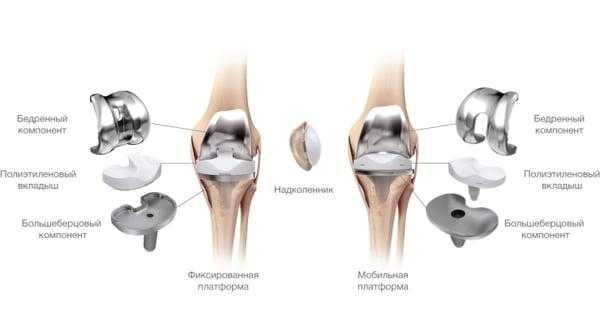

Основной метод лечения - постановка эндопротеза вместо поврежденного сустава. Раньше выполнялось преимущественно тотальное эндопротезирование коленного сустава, однако сейчас активно развивается другое направление - одномыщелковое (частичное) эндопротезирование.

Отличия от тотального эндопротезирования

Длительное время ТЭКС (тотальное протезирование коленного сустава) признавался ведущим методом при лечении остеоартроза. Какие же преимущества имеет одномыщелковое эндопротезирование:

- Гораздо меньший объем хирургического вмешательства;

- Быстрый восстановительный период (уже через несколько месяцев пациент может возвращаться к своим повседневным физическим нагрузкам);

- Менее выражен болевой синдром (как в покое, так и при интенсивной физической нагрузке);

- После частичного эндопротезирования люди вдвое реже жалуются на трудности при использовании автомобиля, чем после тотального;

- Вдвое меньше случаев ограничения сгибания в коленном суставе и контрактур;

- Гораздо чаще людям с частичным эндопротезом доступно положение сидя на корточках, посадка и выход из автотранспорта, наклон и подъем предметов с пола, бег.

Целый ряд неоспоримых и важных преимуществ однополюсного протезирования. Большинство зарубежных коллег подчеркивают у себя схожесть приведенных результатов.

Сравнение двух типов операций.